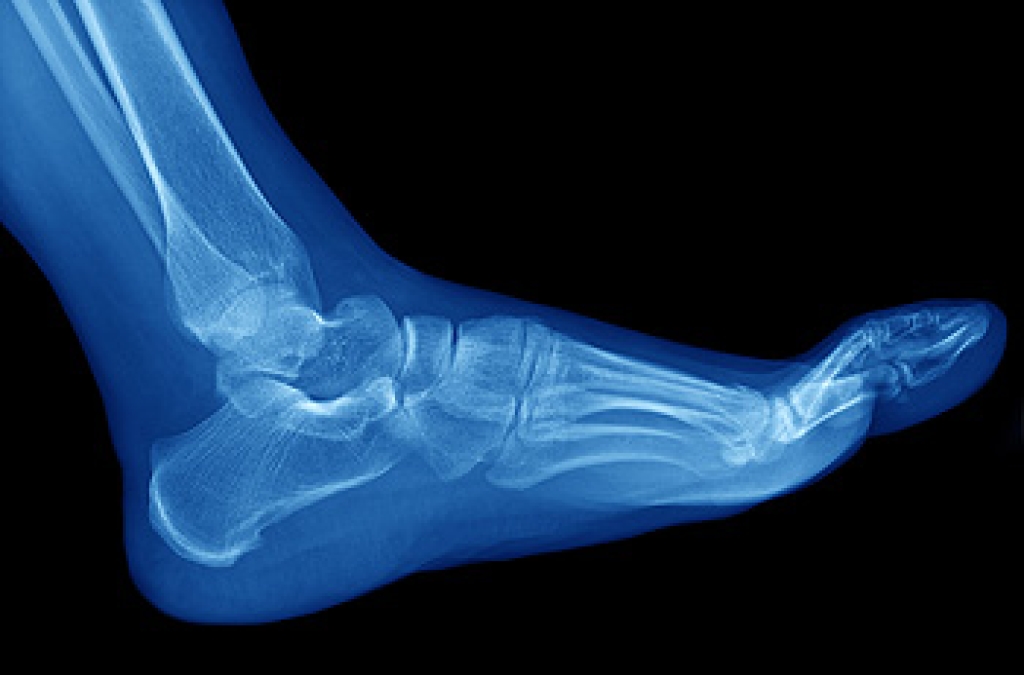

The foot condition known as gout has affected millions of people worldwide. It generally occurs in middle-aged people, and it may result from specific medications. Gout can occur from eating foods that contain high levels of purines, including shellfish, red meat, and drinks made with large amounts of sugar. The excess purines convert to uric acid and can cause crystals to form in the joints of the big toe. The pain from gout can be debilitating, and it is often difficult to walk. Effective prevention methods for gout include drinking plenty of water daily, eating healthy foods, and frequently engaging in a gentle exercise routine. A diagnosis can consist of extracting a small sample of the fluid from between the joints of the big toe, followed by receiving proper relief and treatment techniques. If you experience gout attacks, it is strongly advised that you are under the care of a podiatrist who can help you to manage this condition.